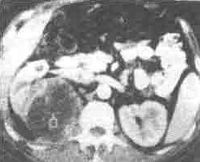

(5)肾脏超声波检查是肾周脓肿的一种诊断性检查方法,但CT扫描更能反映病变的全貌。CT的表现有软组织肿块,其中CT值下降至0~20H单位,在无造影剂增强的情况下,炎性脓肿壁CT值下降稍多;注射造影剂后,脓肿壁密度增强,周围组织结构层次消失,病侧肾脏或腰大肌扩大,肾周筋膜增厚,病灶内出现气体或气液平面。在CT引导下经皮穿刺可确定诊断并可查清致病菌

肾周脓肿CT